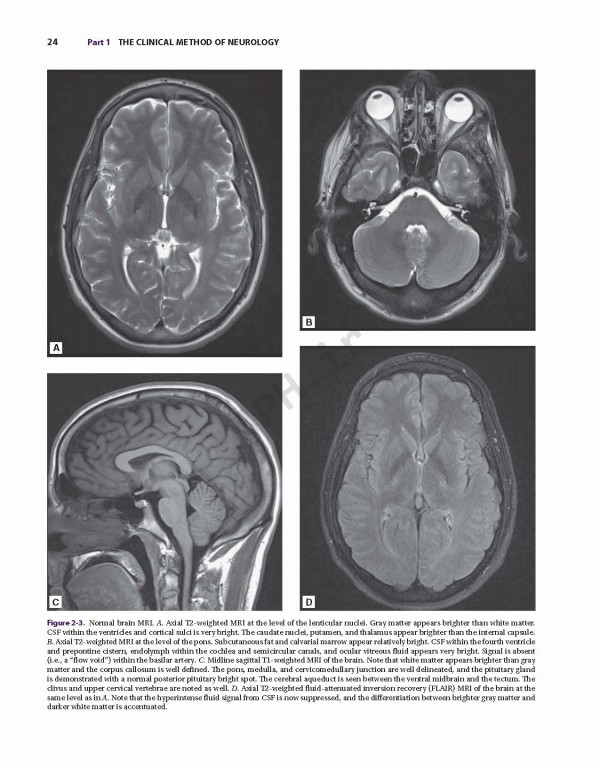

کتاب Adams and Victor's Principles of Neurology 11th Edition 2019، اصول نورولوژی آدامز و ویکتور یک کتاب مشهور که پزشکان را به درک عمیق از جنبه‌های اصلی بیماری عصبی، از جمله داده‌های بالینی و جدید علمی راهنمایی می کند. این متن دقیق و تجدید نظر شده و به روز شده‌، همچنان یک شاهکار در زمینه خود است و خواندنی ترین مرجع موجود. در صفحات آن، شما می توانید توصیفات انضباطی از داده‌های بالینی و توضیحات روشنی از روند بیماری‌های زمینه‌ای را پیدا کنید.

Adams and Victor’s Principles of Neurology is truly the classic text in its discipline --- a celebrated volume that guides clinicians to an in-depth understanding of the key aspects of neurologic disease, including both clinical and new scientific data. This meticulously revised and updated text remains the masterwork in its field, and the most readable reference available. Within its pages, you will find a disciplined presentation of clinical data and lucid descriptions of underlying disease processes.

•A rich, full-color presentation that includes many high-quality illustrations